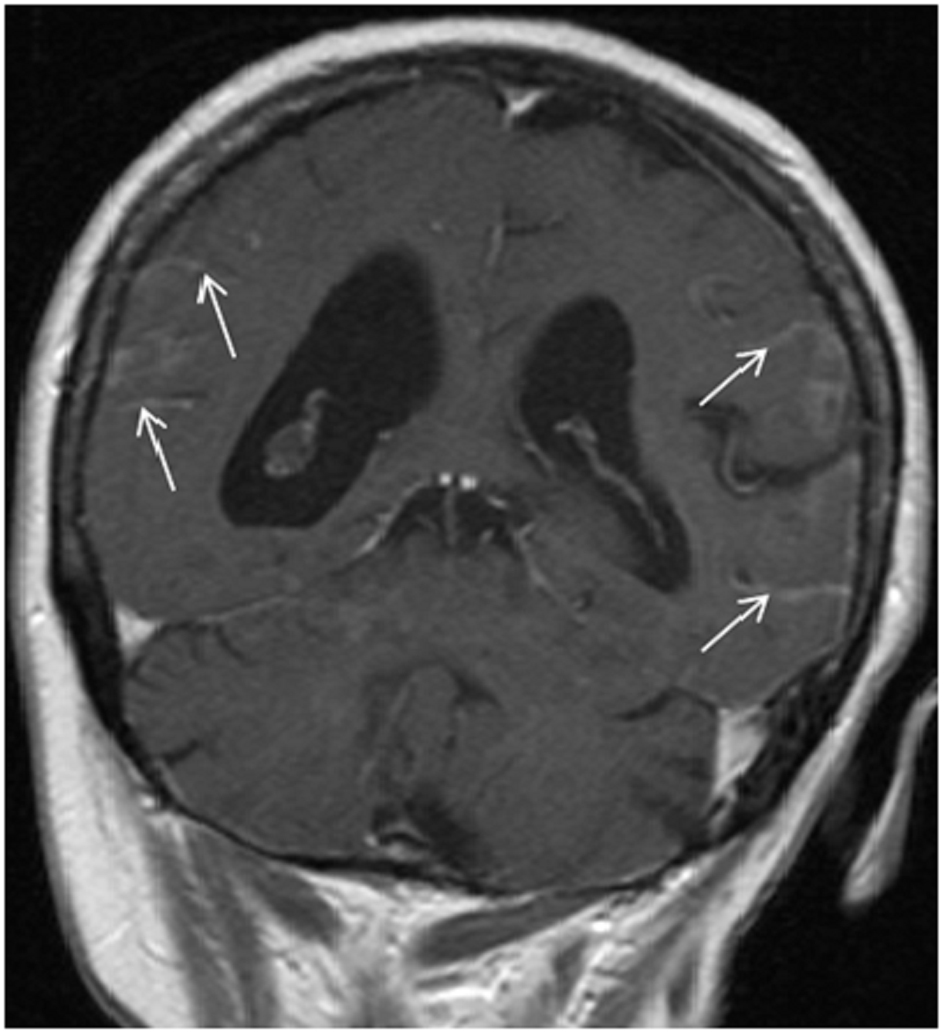

A 66-year-old woman presented with a 2 weeks history of fever, exertional dyspnea and generalized weakness. Physical examination was unremarkable except for temperature of 38.7°C and scattered ecchymoses. Complete blood count revealed WBC of 26.5 × 109/L with 75% blasts, hemoglobin of 9.1 g/dL, platelet of 15 × 109/L and lactate dehydrogenase (LDH) of 2,039 IU/L. Peripheral smear revealed immature cells with irregular, lobulated nuclear contour, scant cytoplasm, fine granules and occasional Auer rods. Bone marrow aspiration and biopsy confirmed the diagnosis of microgranular variant of APL. Cytogenetic and molecular testing detected the presence of bcr3 of PML-RARα consistent with t(15;17)(q22;q21). She was initiated on induction therapy with all-trans retinoic acid (ATRA) 45 mg/m2 twice daily until complete remission (CR) and idarubicin 12 mg/m2 daily on day 2, 4, 6 and 8 [3]. Unfortunately, treatment course was complicated by subarachnoid hemorrhage (SAH) and severe differentiation syndrome requiring mechanical ventilation and interruption of therapy on day 5. She subsequently recovered and resumed induction therapy with single agent ATRA and achieved complete cytogenetic and hematological remission but molecular remission was not confirmed. Due to a poor performance status, she was not a candidate for consolidation chemotherapy and therefore, received consolidation therapy with ATRA for 8 cycles and arsenic trioxide (ATO) for 4 cycles [4]. Two months after completion of therapy, she developed progressive headaches and severe photophobia. At that time, WBC was 6.6 × 109/L with no abnormal cells, hemoglobin of 12.3 g/dL, platelet of 227 × 109/L and LDH of 146 IU/L. Magnetic resonance imaging (MRI) of the brain showed extensive leptomeningeal enhancement (Fig. 1). Cerebrospinal fluid (CSF) was very cellular with many immature cells with morphology similar to that seen in the bone marrow at initial diagnosis (Fig. 2). Additionally, flow cytometry detected a similar immunophenotype to that noted at initial diagnosis. Despite continued hematological and cytogenetic remission, reverse transcription polymerase chain reaction of peripheral blood detected the brc3 isoform of PML-RARα confirming molecular relapse. She was treated with repeated courses of intrathecal methotrexate and cytarabine. With therapy, she showed clinical improvement and resolution of her symptoms with clearance of her CSF. Systemic therapy was deferred to the outpatient setting given her poor performance status. She was non-compliant and lost to follow-up.

![]() Click for large image | Figure 1. T1-weighted MRI image showing leptomeningeal enhancement (arrows). |